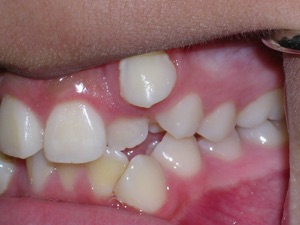

Here is what he looked like on the day that the braces were removed.

In the final photo, you can see the bonded retainer we used. A top nighttime removable retainer was made.